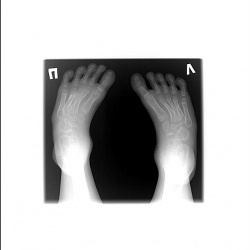

Hallus valgus 1 пальца левой стопы. Как грамотно описать?

Добрый день! Коллеги, я все о стопах. Выскажите , пожалуйста, свое мнение о плоскостопии и степени артроза в таранно-ладьевидном суставе данного молодого человека. В анамнезе...